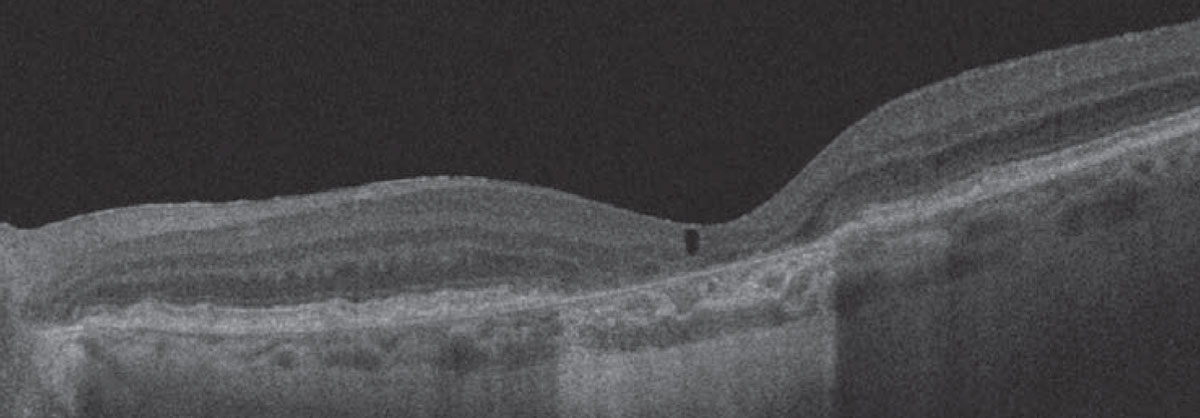

One hypothesis regarding this nonexudative fluid states that it may be due to transudative mechanisms, such as disrupted Müller cells or retinal pigment epithelial pump failure.1 Cystoid, or cavitary, spaces can occur over areas of atrophy as a result of the retinal degeneration process, possibly secondary to Müller cell degeneration (Figure 1).2

![]() |

| Figure 1. Optical coherence tomography demonstrates an area of subfoveal atrophy in a case of non-neovascular age-related macular degeneration with overlying cystoid degeneration. |